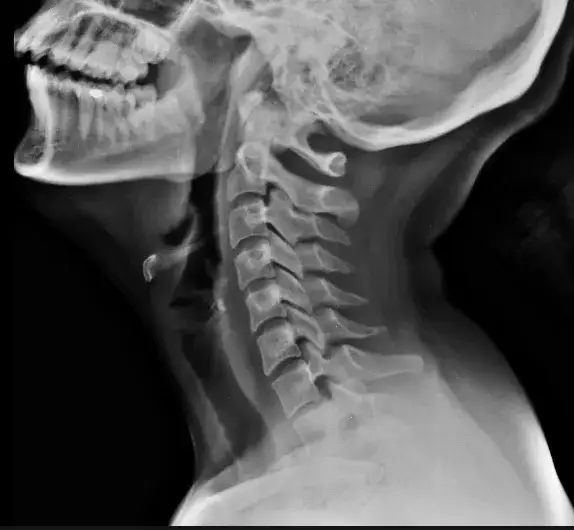

- Diagnostyka obejmuje wywiad, badanie fizykalne i badania obrazowe (RTG, MR, TK), a leczenie opiera się na farmakoterapii i fizjoterapii.

Proces diagnostyczny skręcenia karku jest wieloetapowy i ma na celu nie tylko potwierdzenie urazu, ale przede wszystkim wykluczenie poważniejszych uszkodzeń, takich jak złamania kręgów czy dyslokacje. Zaczyna się od szczegółowego wywiadu, podczas którego lekarz zapyta o okoliczności urazu, objawy i historię medyczną. Następnie przeprowadzi badanie fizykalne, obejmujące ocenę neurologiczną (sprawdzenie odruchów, czucia, siły mięśniowej) oraz ortopedyczną (ocena ruchomości szyi, palpacja bolesnych miejsc). W celu dokładniejszej oceny i wykluczenia poważniejszych urazów, lekarz zleci badania obrazowe. Najczęściej jest to RTG kręgosłupa szyjnego, czasem w projekcjach czynnościowych (przy ruchach zgięcia i wyprostu) lub przez otwarte usta (do oceny pierwszych kręgów). W przypadku podejrzenia uszkodzenia tkanek miękkich, rdzenia kręgowego lub dysków, niezbędny może okazać się rezonans magnetyczny (MR), a w celu dokładnej oceny struktur kostnych tomografia komputerowa (TK). To kompleksowe podejście pozwala na postawienie trafnej diagnozy i zaplanowanie skutecznego leczenia.